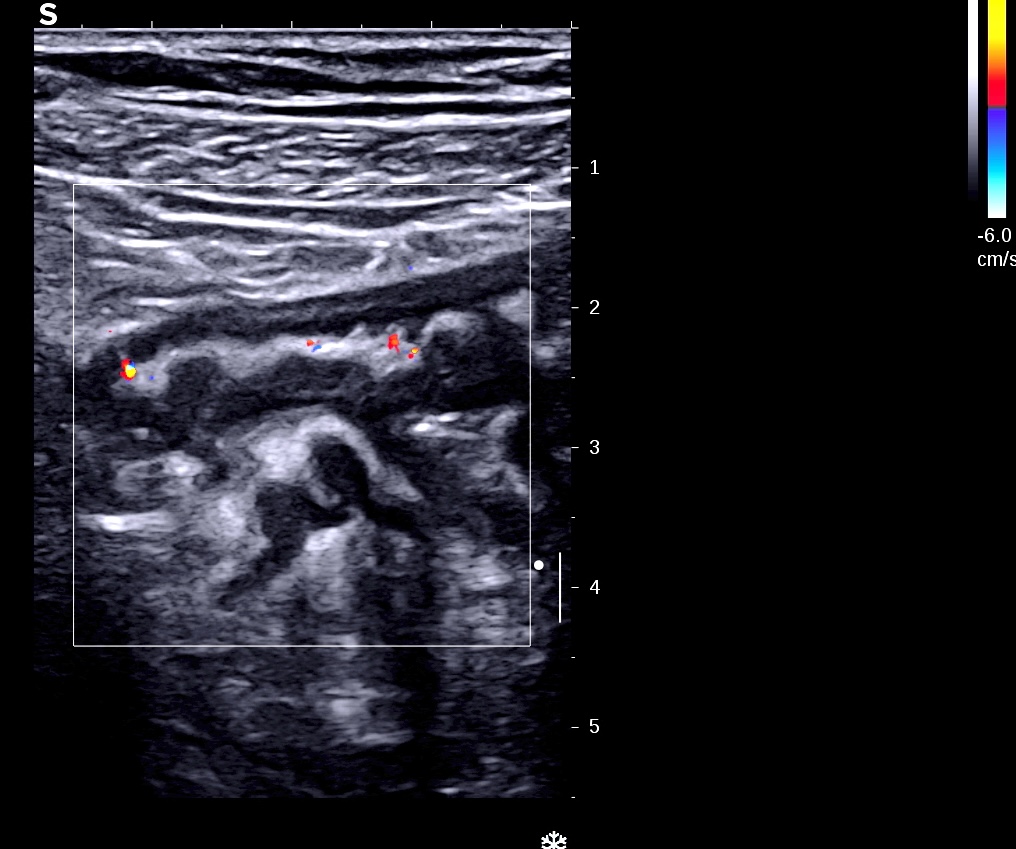

Le doppler est souvent limité à la paroi (Limberg 1 et 2), la graisse peu ou pas infiltrée

Les ganglions sont de petite taille

Malgré sa petite taille, ganglion rond, hypoéchogène donc inflammatoire